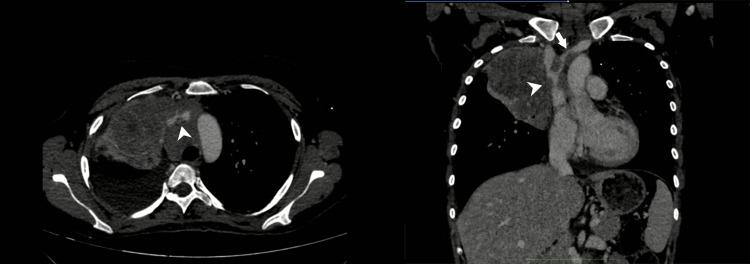

Superior vena cava syndrome (SVCS) is a clinical entity characterized by signs and symptoms arising from the obstruction or occlusion of the thin-walled superior vena cava (SVC) and can result in significant morbidity and mortality. Despite the rise of benign cases of SVCS, as a thrombotic complication of intravascular devices, it is most commonly seen secondary to malignancy as a consequence of thrombosis, direct invasion of tumor cells inside the vessel, or external compression. SVCS can be the initial presentation of a previously undiagnosed tumor in up to 60% of cases. Lung cancer and non-Hodgkin lymphoma (NHL) are responsible for up to 85%-90% of malignancy-related SVCS, while metastatic cancers account for approximately 10%. Herein, we review the pathophysiology, etiology, clinical presentation, diagnosis, and management of malignancy-related SVCS.